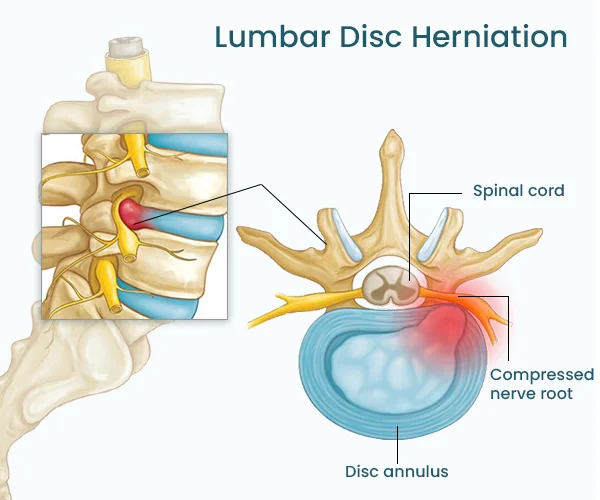

Spinal Disc Herniation Physical Therapy focuses on relieving pressure caused by herniated or bulging spinal discs. At Advanced Spinal Care, we use a combination of physical therapy techniques, spinal decompression, and chiropractic care to reduce inflammation, improve mobility, and help the disc heal naturally. The goal is to ease nerve compression and get you moving comfortably again—without invasive procedures.

Spinal Disc Herniation Physical Therapy is recommended if you’re experiencing back pain, numbness, tingling, or weakness due to a herniated disc. It’s especially effective for patients looking to avoid surgery or long-term medication. Whether your injury came from an accident, repetitive strain, or degeneration over time, treating it early can prevent it from getting worse.